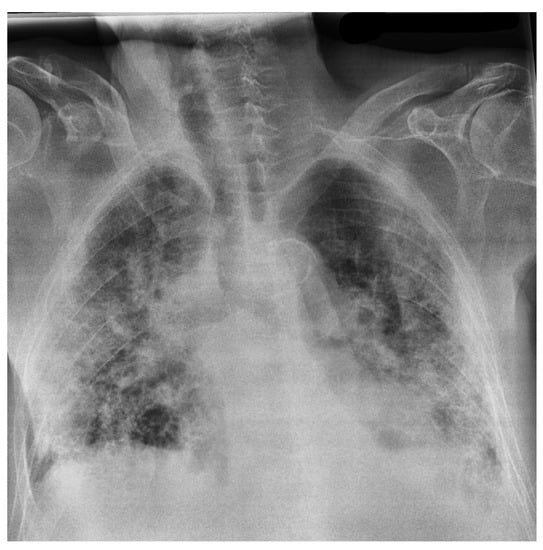

Figure 8 and Figure 9 display four original pulmonary radiographs—two of patients diagnosed with COVID-19 and two of uninfected people. Each of these images was properly predicted with the derived classifier. For each of these images, the corresponding SHAP values were computed, and the results are illustrated in Figure 10, Figure 11, Figure 12 and Figure 13.

On the other hand, Figure 12 and Figure 13 show the SHAP values computed for the cases of Figure 9, which were classified as NORMAL. In these cases, the mid plots show the zones of magenta pixels that convey relevant information for classifying the images as NORMAL. Accordingly, if these images were classified as images of lungs infected with COVID-19, these same zones would attain very low SHAP values, as illustrated in the bottom plots of Figure 12 and Figure 13.

Figure 9. Examples of radiography images of patients not infected with COVID-19 (negative examples).